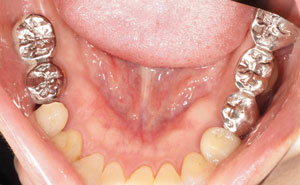

@@R.S‚³‚ñ@56Î —«  ‘åŠw‹³Žö @Žèp“ú@‚Q‚O‚O‚W”N ‚QŒŽ ‚X“úi“yj@㉺Š{  ƒm[ƒxƒ‹ƒKƒCƒhŽg—p@Ö¬“à’ÁÖ@•¹—p@@@

@@@@@ãŠ{  All on ‚U@‘¦Žž‰Ád@@

@@@@@@@@@@@@@ Rpl Tapered Rp  ‚P‚O mm(‚U–{)

@@@@@‰ºŠ{¶‰E@‘¦Žž‰Ád@ ‚R Unit Bridge@

@@@@@@@@@@@ @Rpl Tapered Rp  ‚P‚O mm(‚S–{)@@–ƒWƒ‹ƒRƒjƒAƒNƒ‰ƒEƒ“‚ÅÅI•â’Ô